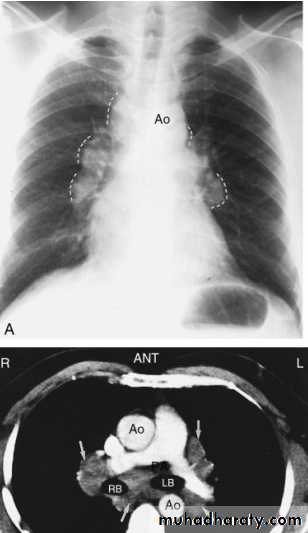

Sarcoid.

Marked lymphadenopathy (dotted lines) is seen in the region of both hila in the right paratracheal region (A).The transverse contrast-enhanced computed tomography scan of the upper chest (B) clearly shows the ascending and descending aorta (Ao) as well as the pulmonary artery (PA) and superior vena cava. The right and left main-stem bronchus area also is seen. Arrows, the extensive lymphadenopathy.